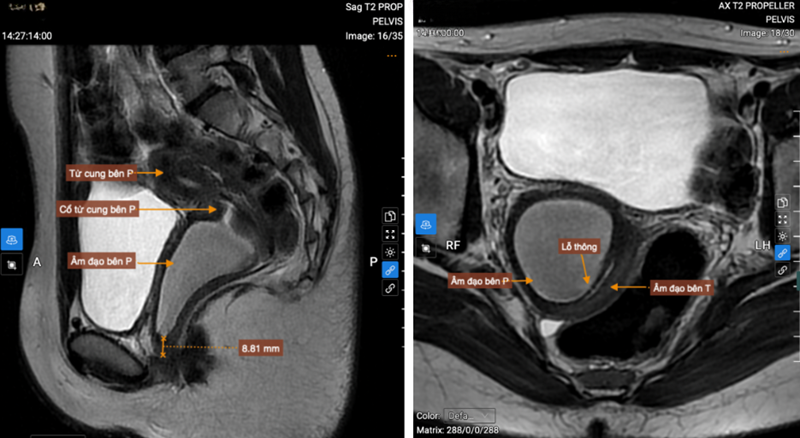

Trên MRI cho thấy 2 sừng tử cung, 2 cổ tử cung riêng biệt, vách ngăn âm đạo

Âm đạo bên phải ứ dịch (kích thước 75x40mm), âm đạo bên trái xẹp, theo dõi có lỗ thông nhỏ, vị trí tắc cách tiền đình âm đạo 9mm

Kết quả siêu âm ổ bụng và MRI tiểu khung ghi nhận: hình ảnh tử cung đôi hoàn toàn; vách ngăn âm đạo kèm ứ đọng dịch máu trong nửa phải âm đạo; thận phải loạn sản đa nang, lạc chỗ.